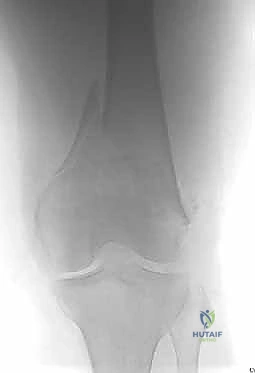

- الأشعة السينية (X-Rays): أخذ صور من زوايا متعددة (أمامي خلفي، وجانبي) لتحديد موقع الكسر ونوعه.

- الأشعة المقطعية (CT Scan): وهي ضرورية جداً في كسور عظم الفخذ البعيدة، خاصة إذا كان الكسر يمتد إلى داخل مفصل الركبة (Intra-articular fractures). تساعد الأشعة المقطعية الدكتور هطيف على بناء نموذج ثلاثي الأبعاد للكسر، مما يسهل التخطيط الجراحي وتحديد أماكن وضع المسامير بدقة.